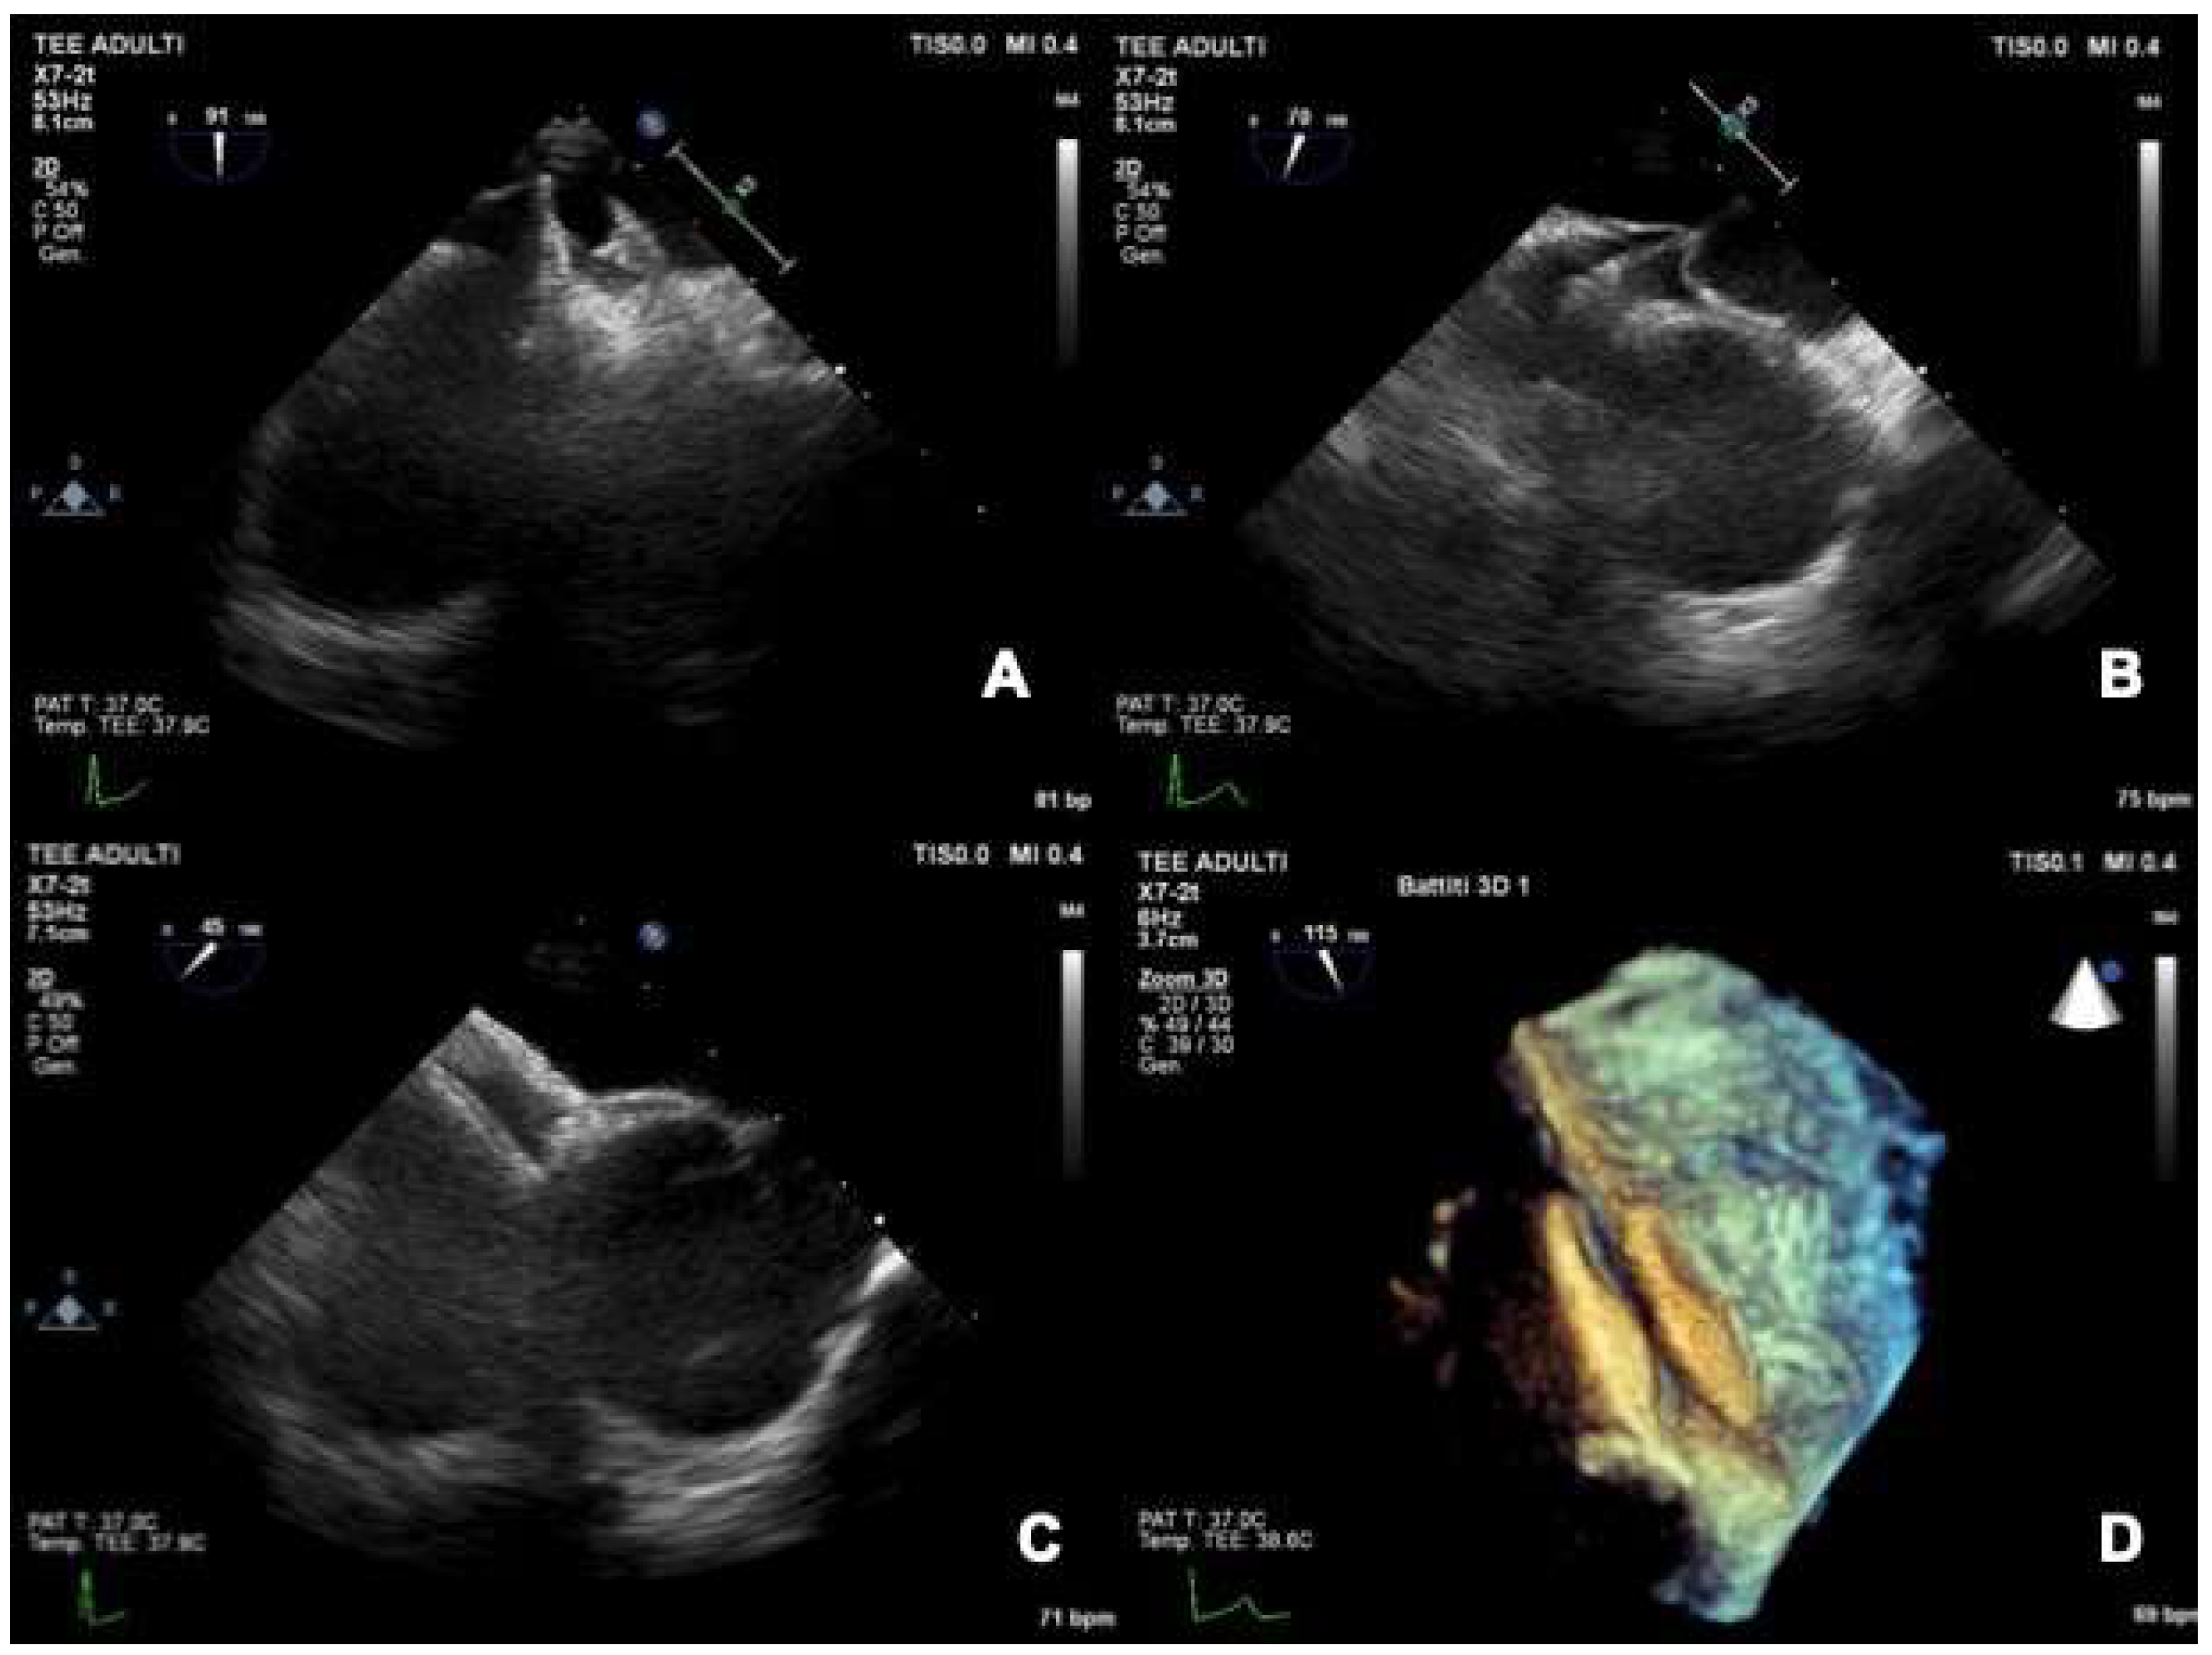

2.3.2. TEE during PFO Closure: Intra-Procedural Guidance

4.2. Role of TEE